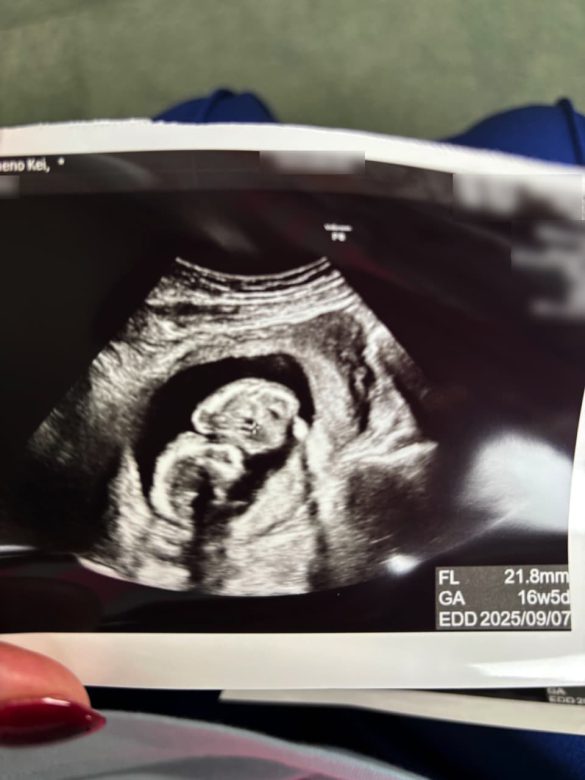

産婦人科へ行くと初老の男性医師が診てくれた。内診台に上がると医師が「あれ? 大きい……」とつぶやく。大きいってどのくらい……? そのままエコー検査を受けると、モニタに胎児が映し出された。すでに頭や体の形がわかるまで成長している。